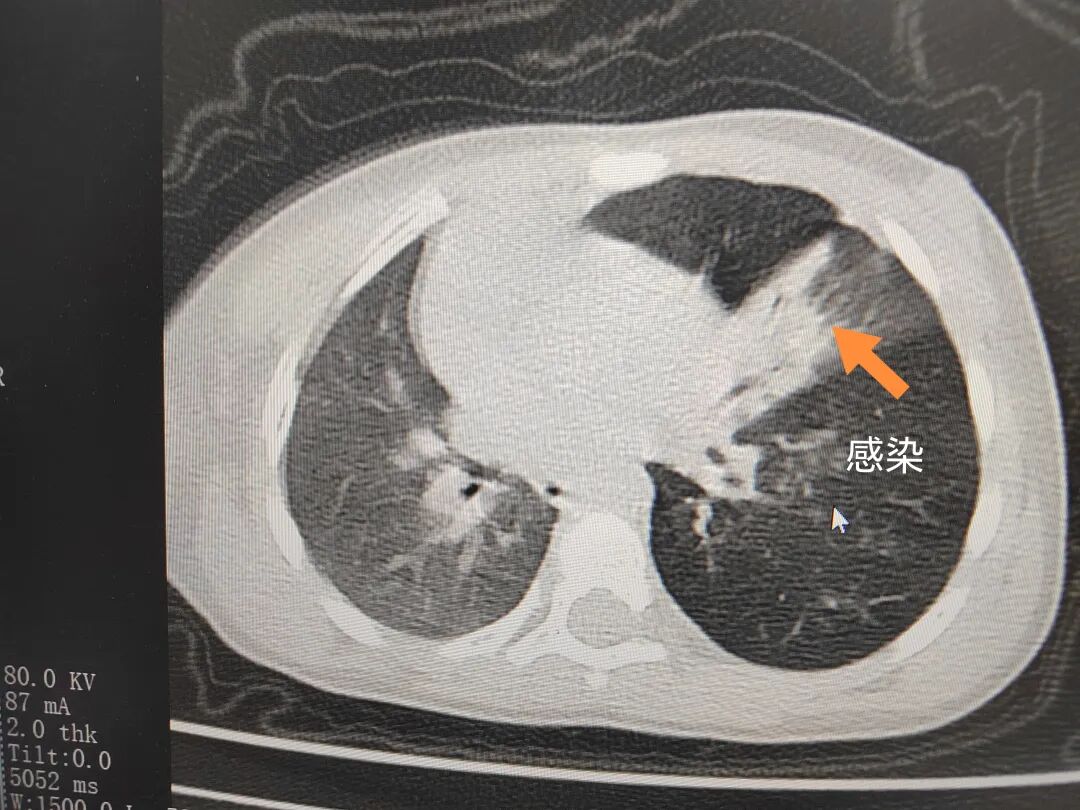

三天后(11月13日),趙寶出現(xiàn)高熱、咳喘加重,家長著急了,再次帶他來到醫(yī)院。CT檢查顯示左肺過度充氣,左肺上下葉支氣管主干見不規(guī)則高密度影,左肺上葉可見大片狀密度增高影,縱隔窗實變,提示為“左側(cè)支氣管內(nèi)異物并繼發(fā)性改變,左肺上葉舌段肺膨脹不全”。

市二院小兒呼吸內(nèi)科團隊迅速為患兒制定了周密的手術(shù)方案,并很快安排了氣管鏡探查。術(shù)中,主治醫(yī)師田慧等憑借嫻熟的氣管鏡操作技術(shù)成功將異物大塊板栗取出。由于板栗在氣管內(nèi)存留時間較長,質(zhì)地軟糯易碎,大大增加了手術(shù)難度。檢查還發(fā)現(xiàn),異物停留部位的氣管黏膜已出現(xiàn)充血紅腫、糜爛,導致患兒住院時間相應延長。此次事件給趙寶的家庭帶來了不小的驚嚇與擔憂,也再次為廣大家長敲響了警鐘。

市二院小兒呼吸內(nèi)科副主任楊亞娟介紹,異物誤入氣道可能導致氣道阻塞,嚴重時可引發(fā)窒息,甚至危及生命。若異物進入支氣管,造成不完全堵塞,可引起阻塞性肺氣腫;如完全堵塞支氣管,則可能導致肺組織萎縮,形成肺不張。此外,若異物存留時間較長,或為植物性異物,容易合并細菌感染,產(chǎn)生膿性分泌物,進而發(fā)展為肺炎。她強調(diào),盡早診斷并取出異物,是減少并發(fā)癥、降低病死率的關(guān)鍵。